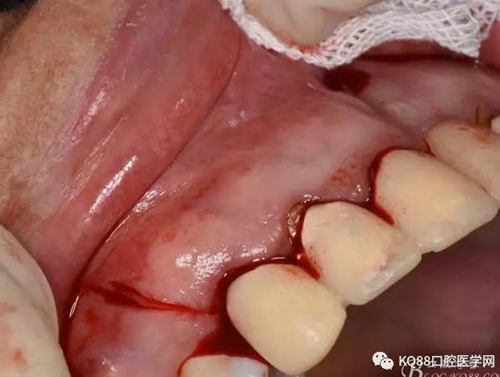

圖7. 分別在13的遠(yuǎn)中和11的近中做垂直切口加齦溝內(nèi)水平切口,形成梯形瓣

圖8.翻開梯形瓣